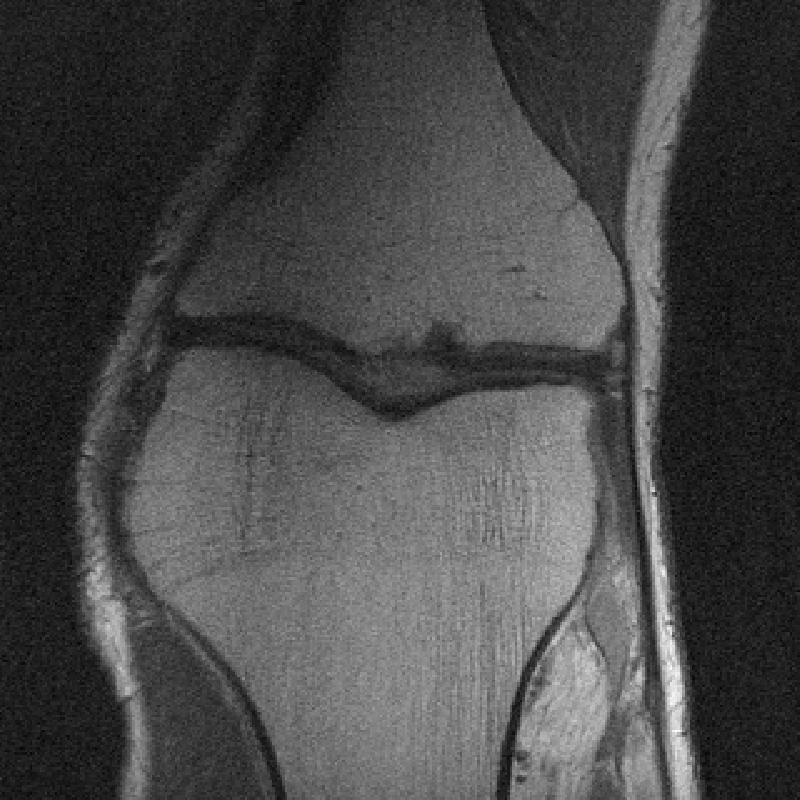

The data used in the undersampled MRI experiments were obtained from the NYU fastMRI Initiative [45]. The primary goal of the fastMRI dataset is to test whether machine learning can aid in the reconstruction of medical images. We trained and tested on a subset of the single-coil knee dataset, which consist of simulated single-coil measurements. In all tests, we use complex-valued data, which interfaces with our deep networks by treating the real and imaginary parts of the images as separate channels. We measure reconstruction accuracy with respect to the center 320320 pixels of the complex IFFT of the fully-sampled k-space data. For the purpose of visualization, we display only the magnitude images in the following sections.

In Table 1 we present our main results. We present sample reconstructions for the deblurring problem and MRI reconstruction problem in Figs. 7 and 8. For reference, the ground truth, inputs to the networks, a total variation regularized reconstruction, and a RED reconstruction are presented in Figs. 5 and 6. We also provide in the Appendix a table of SSIM values as well as the full version of Table 1, which contains the standard deviations of PSNR.

While the magnitude of the improvements vary across domains and problems, we find that retraining the network with the proposed model adaptation techniques significantly improve performance by several dBs in the new setting. This effect is particularly striking in the case of MRI reconstruction with MoDL, where the βnaiveβ approach of replacing with in the network gives catastrophic results (a roughly 9 dB drop in reconstruction PSNR), while the proposed model adaptation approaches give reconstruction PSNRs within 1-2 dB of the baseline approach of training and testing with the same forward model in the case where is known.